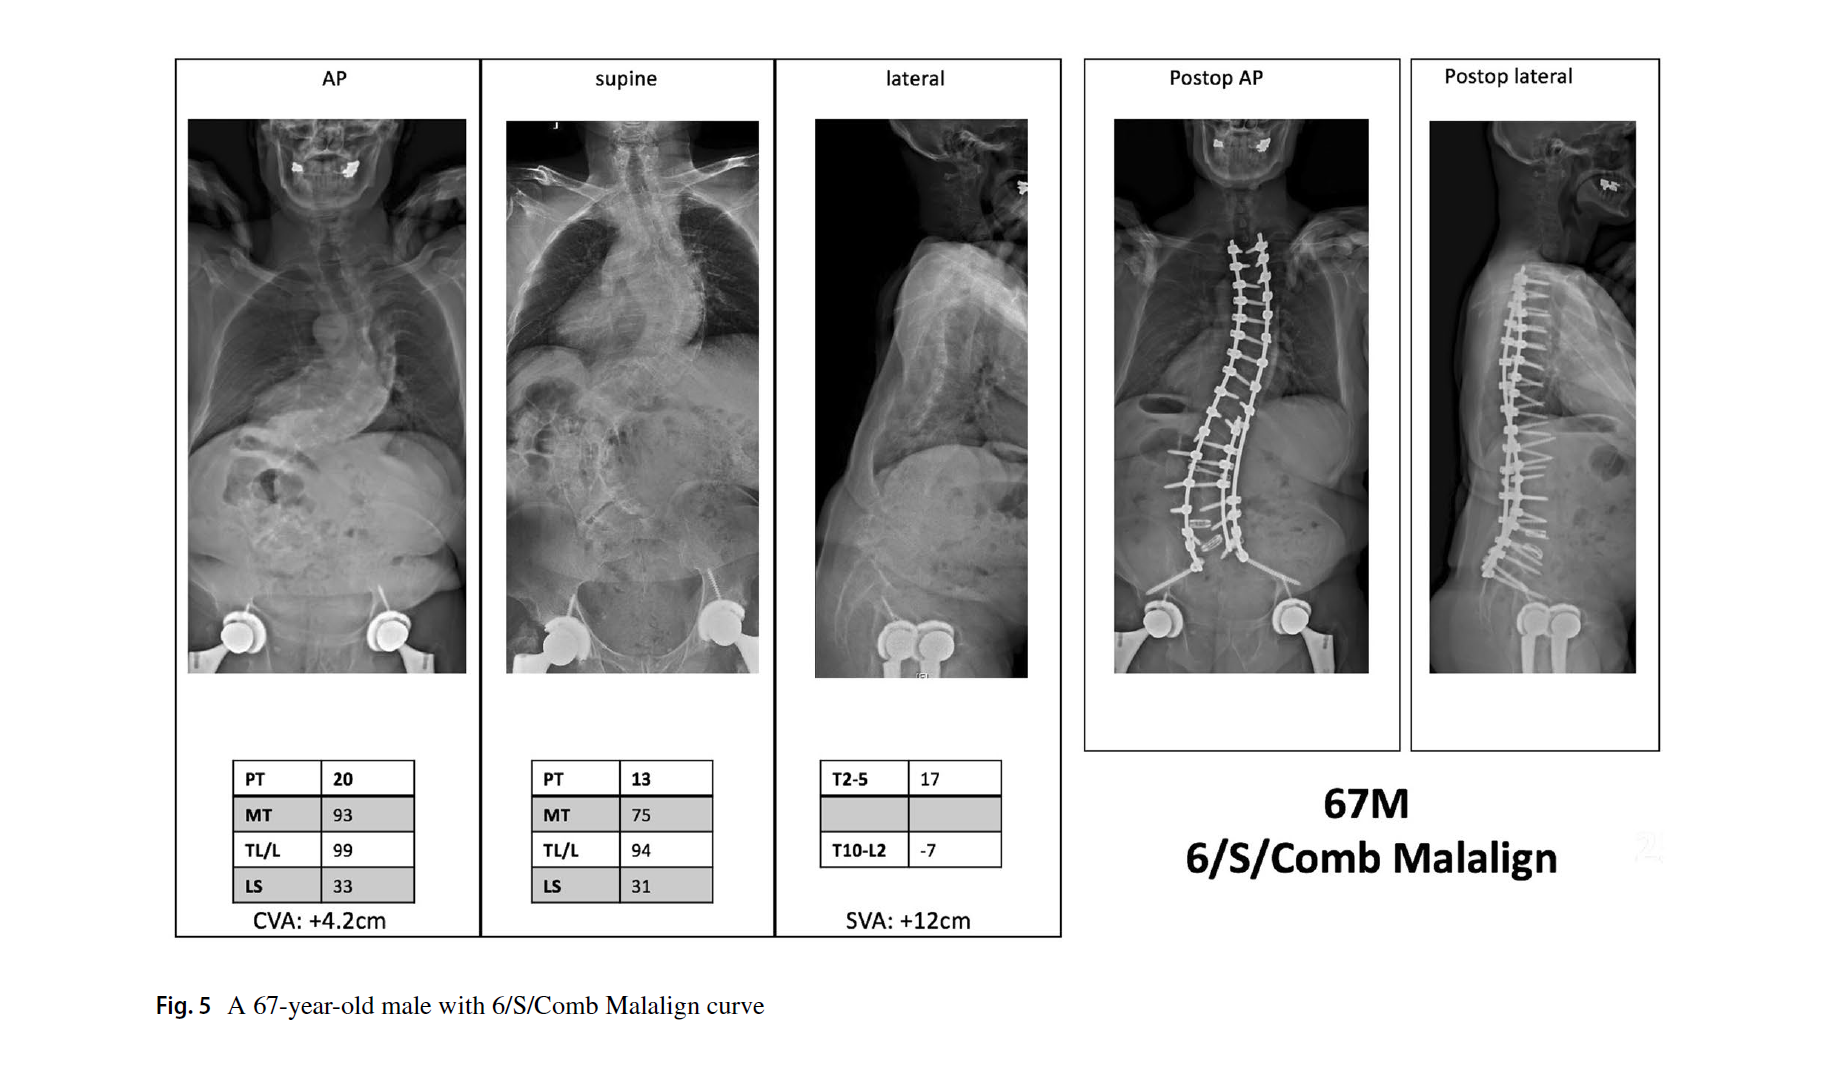

1. 曲线类型分为6型,与Lenke AIS完全一样。但结构弯的标准为:仰卧位全长位Cobb角大于35度,或者后凸大于20度。这与AIS不同,也摒弃了bending位片。

2. 腰骶椎修正,是本分型的特别和关键之处。定义为仰卧位片L4上终板到S1上终板的Cobb角。大于20度为结构弯(S),需要融合腰骶段。小于20度为非结构弯(NS),不需要融合腰骶段。

3. 脊柱平衡修正包括了冠状位、矢状位和冠矢合并的平衡状态。标准与SRS基本一致,冠状位失衡CVA≥40mm,矢状位失衡SVA≥40mm。排列组合,共有Aligned、Sag Malalign、Cor Malalign、or Comb Malalign 4种类型。如果脊柱失衡,需要按SRS标准矫正。

文中的病例片子很漂亮,看图知意,很容易让读者理解这个分型。